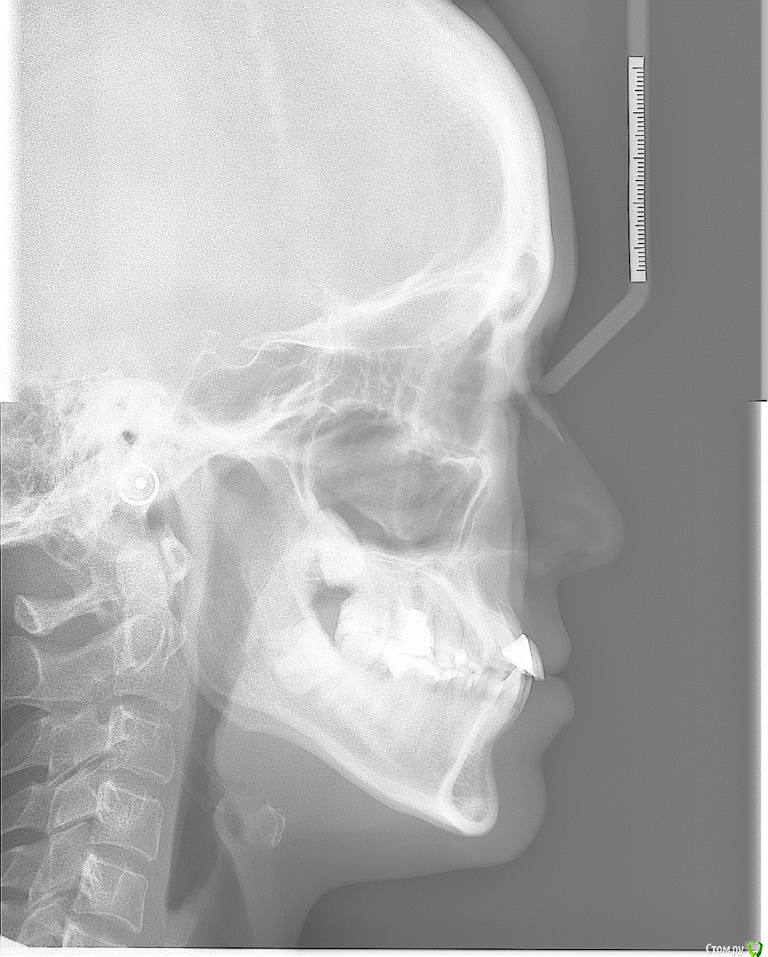

Galaola Опубликовано 28 февраля, 2016 Поделиться Опубликовано 28 февраля, 2016 Добрый день! Мне 36лет. Удалена правая верхняя 4 в детстве. При выборе ортодонта остановилась на варианте без удаления зубов, но с сепарацией зубов НЧ. Через 6 мес лечения ортодонт заявляет об удалении правой нижней 8 как минимум, а лучше всех. Прошу совета и мнения специалистов. Насколько необходимо удаление 8-к? Возможно ли расширить ВЧ и каким образом? Возможно ли подготовить место под имплант отсутствующей 4 или поставить адгезионный мост? Спасибо. Ссылка на комментарий

Galaola Опубликовано 1 марта, 2016 Автор Поделиться Опубликовано 1 марта, 2016 Возможно ли расширить ВЧ и каким образом? Возможно ли подготовить место под имплант отсутствующей 4 или поставить адгезионный мост? без расчетов можно это определить? Ссылка на комментарий